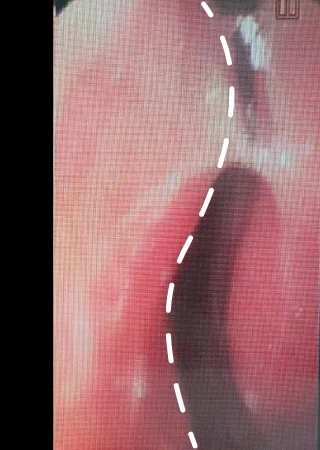

비중격만곡증 수술 Before & After

Natural 숨+ 비중격만곡증 수술 방법

휘어진 곳의 비중격 연골 절개 후 제거

휘어진 비중격 연골을 제거된 공간으로 펴줌

비중격이 완전히 펴진 상태 완성